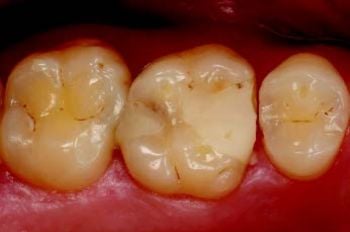

Pasienten hadde en defekt MOD-restaurering på tann 16 med åpen mesialkontakt og sekundær karies distalt (Fig. 1).

Hun rapporterte matansamling og ising. Behandlingsplanen var å erstatte restaureringen med en ny direkte kompositt.

Figur 1 venstre: Tann 16 med sviktende komposittrestaurering, åpen kontakt luftabrasjon og tilbakevendende karies.